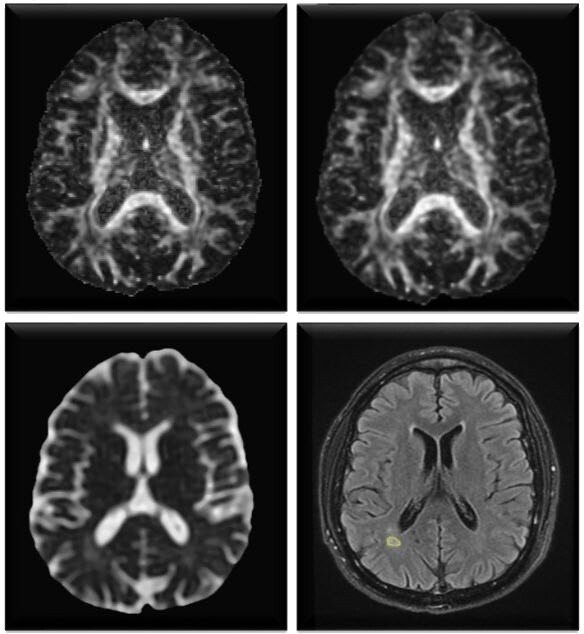

背景:多发性硬化症(MS)是一种慢性神经炎症,以中枢神经系统脱髓鞘和轴突损伤为特征。弥散张量成像(DTI)可对白质的微观结构改变进行非侵入性研究,而血清神经丝轻链(NFL)有望成为轴突损伤的液体生物标志物:方法:41 位复发缓解型多发性硬化症患者和 41 位年龄匹配的健康对照者接受了包括 DTI 采集在内的脑磁共振成像检查。使用 ELISA 分析血清样本中的 NFL 浓度。进行感兴趣区分析以得出 DTI 指标,包括分数各向异性、平均扩散率、轴向扩散率和径向扩散率。相关分析用于探讨成像和生化指标之间的关联:结果:与对照组相比,患者的血清 NFL 水平明显升高,DTI 指标也发生了改变,这表明患者存在轴突/髓鞘病变。DTI 参数与血清 NFL 浓度呈正相关(p 值):结合 DTI 和血清 NFL 测量可提供互补的体内和生化视角,从而加强对多发性硬化症轴突损伤的评估。在这两种测量模式之间观察到的相应变化支持它们作为反映多发性硬化症病理生理过程和临床状态的非侵入性生物标记物的实用性。要确定其临床适用性,还需要更大规模的验证队列。

Methods: 41 patients with relapse-remitting MS and 41 age-matched healthy controls underwent brain MRI including DTI acquisition. Serum samples were analysed for NFL concentrations using ELISA. Region of interest analysis was conducted to derive DTI metrics including fractional anisotropy, mean diffusivity, axial diffusivity and radial diffusivity. Correlational analyses were used to explore the associations between the imaging and biochemical indices.

Results: Patients exhibited significantly elevated serum NFL levels and altered DTI metrics compared with controls, indicative of axonal/myelin pathology. DTI parameters were positively correlated with serum NFL concentration (p value<0.0001). Visual analogue scale scores demonstrated a significant positive relationship between DTI metrics and NFL, validating their potential as radiological and fluid-based markers of symptom severity.